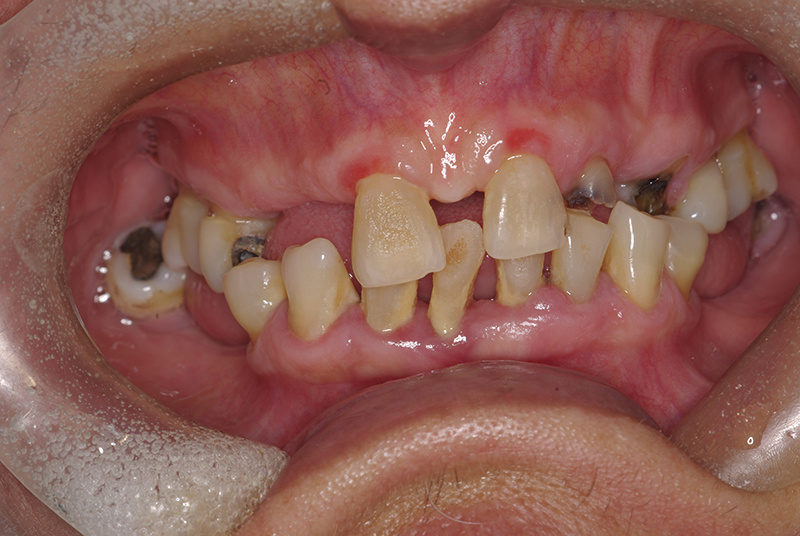

A Carga Imediata é uma técnica odontológica avançada que permite a colocação de uma prótese dentária fixa logo após a cirurgia de instalação dos implantes ou em poucos dias. Isso elimina a espera tradicional de meses para a integração completa do implante ao osso, oferecendo uma solução rápida e segura para restaurar dentes perdidos.

- Avaliação Inicial: Um exame detalhado da saúde bucal e da qualidade óssea do paciente é realizado.

Embora seja uma solução moderna, nem todos os pacientes são candidatos ideais para a Carga Imediata. O sucesso do tratamento depende de fatores como:

- Quantidade e qualidade do osso disponível.

- Ausência de infecções ou doenças periodontais ativas.

- Condições gerais de saúde que favoreçam a cicatrização.

Por isso, uma avaliação personalizada com um especialista é essencial para determinar se a técnica é indicada para o seu caso.